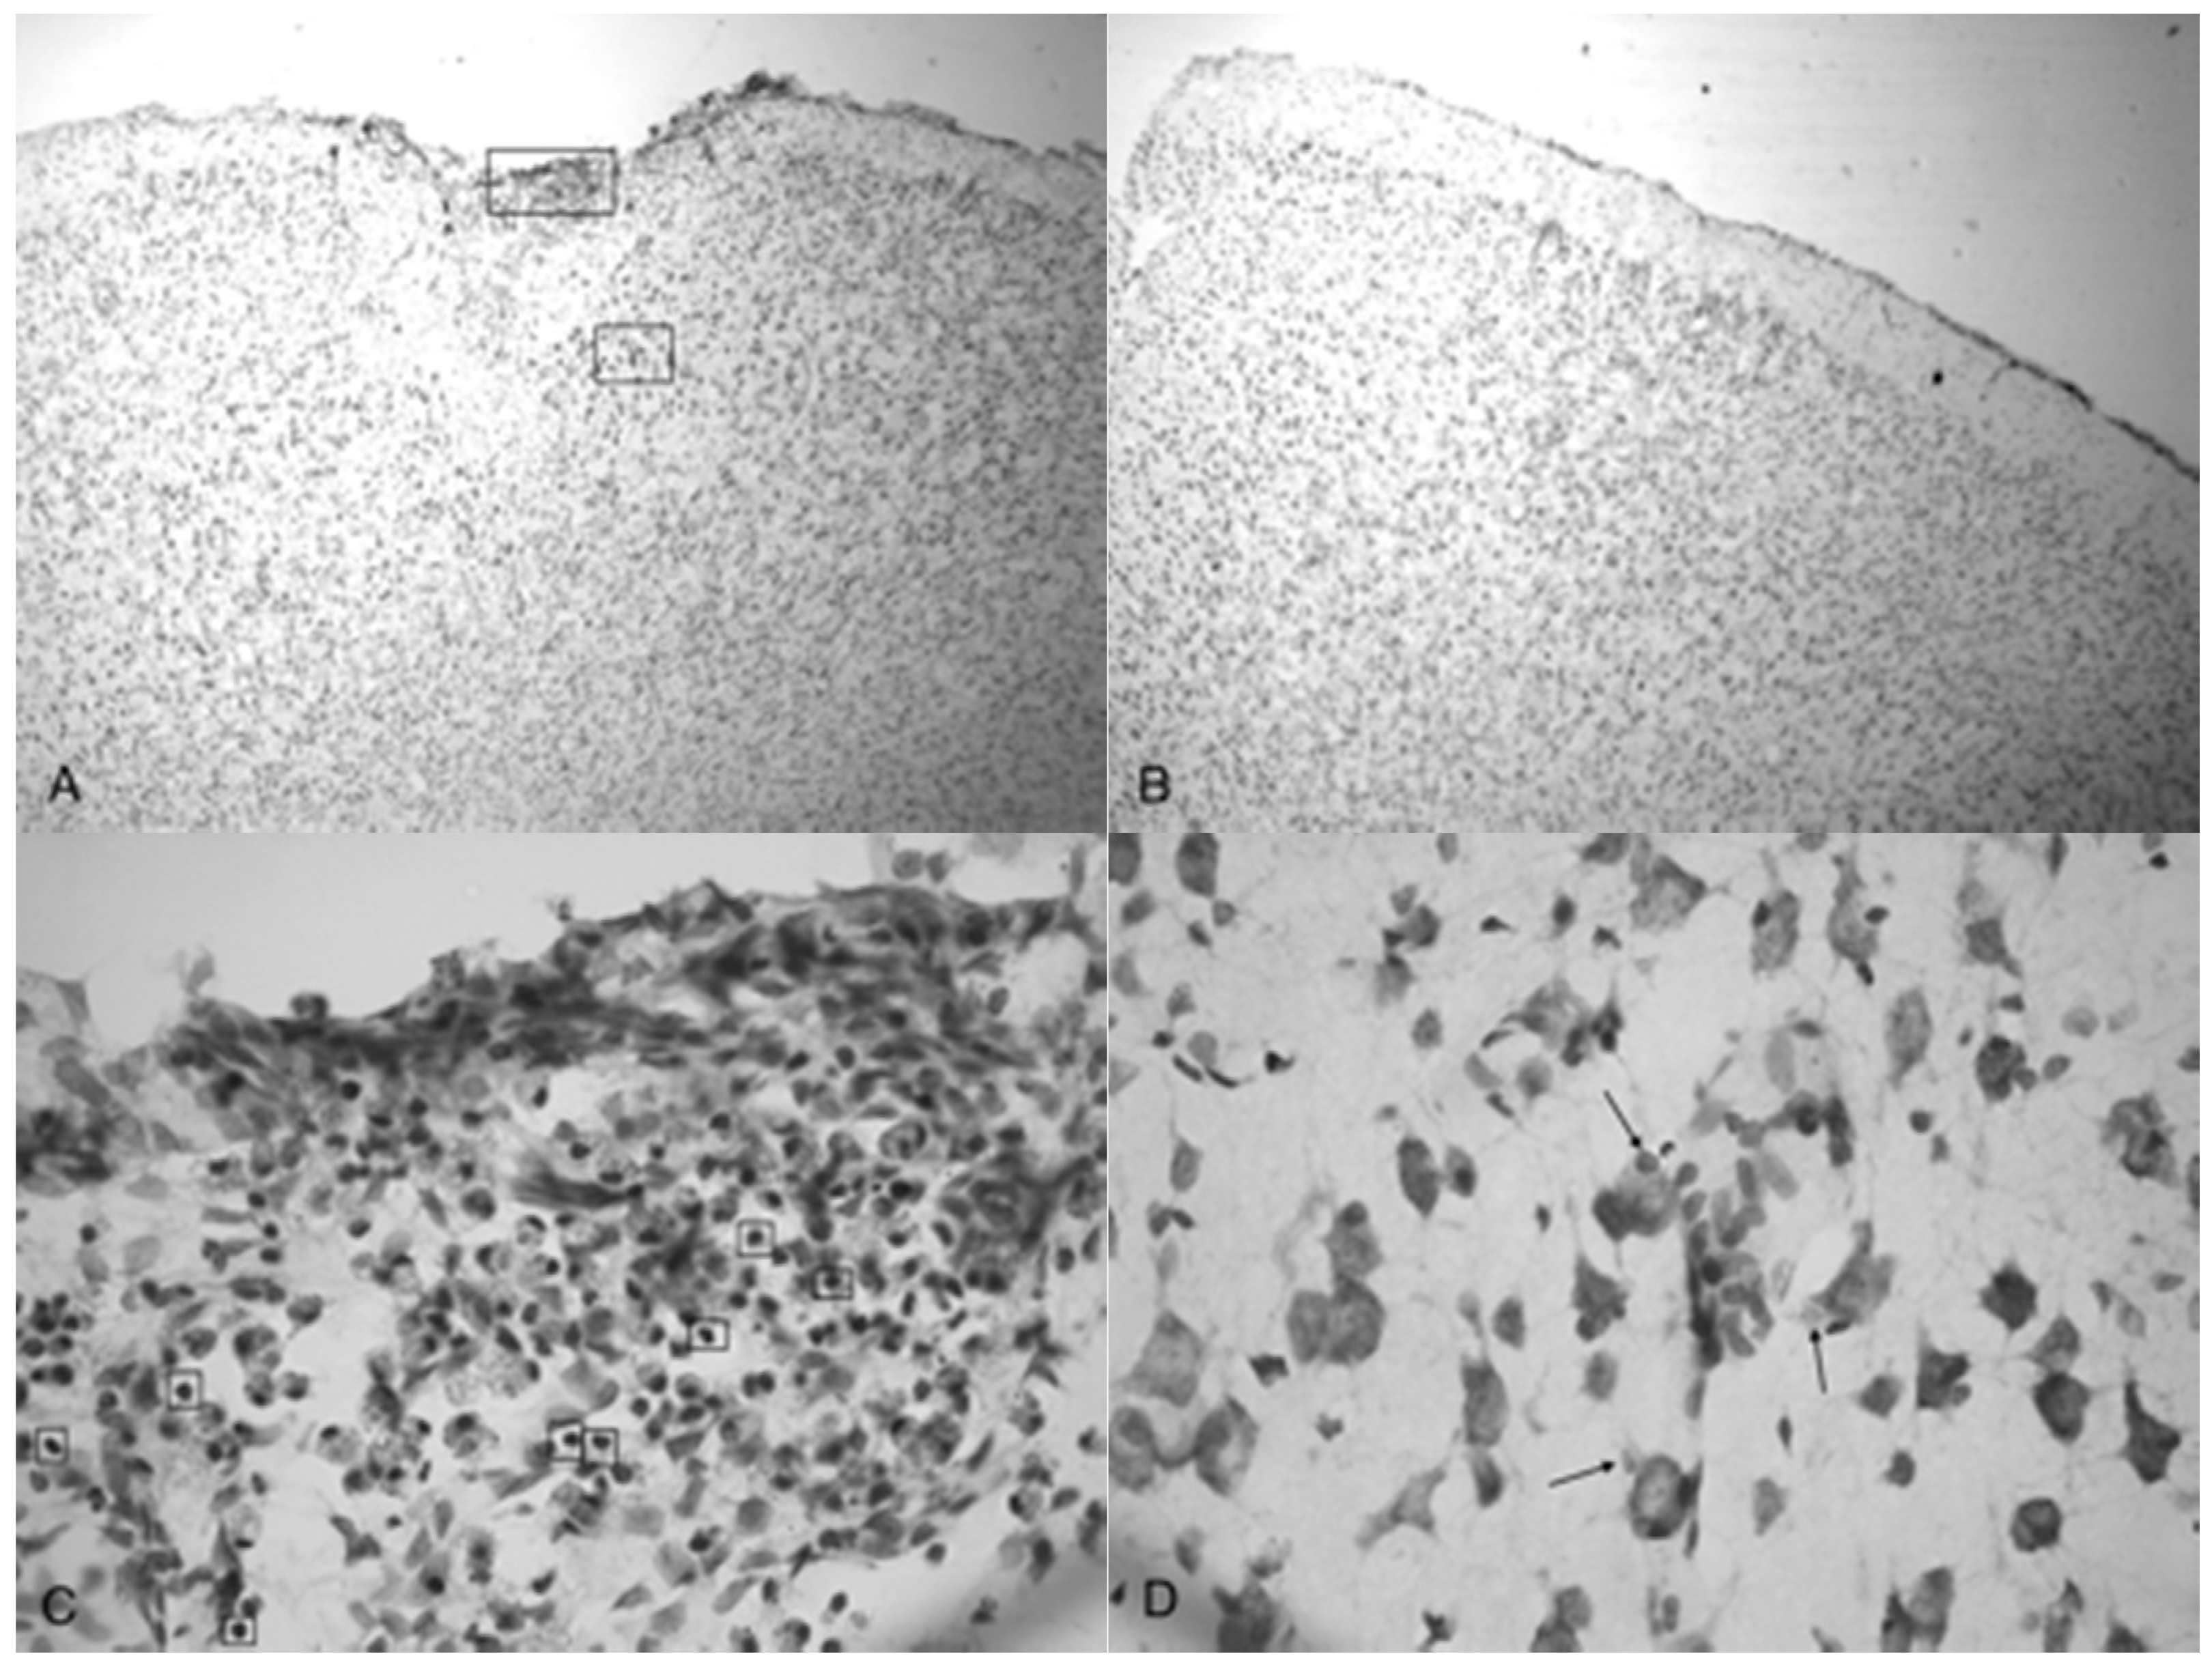

Figure 5A shows the TBI-targeted left frontal cortex 10 days after 5.0 bar acoustic wave treatment. Note the severely damaged cortex compared to 3.4 bar treatment cortex (see Figure 4A,C). While the histology from the 3.4 bar treatment revealed moderate impairment of the dura mater and the arachnoid layer, the 5.0 bar treatments showed significantly more damage to post-TBI tissue that ranges well beyond the pia mater. The intact contralateral cortex showed no damage (Figure 5B). Also, no additional damage was detected in any other brain region of the TBI-treated rats, including the hippocampus.

Figure 5C,D are higher magnification photomicrographs taken from the highlighted regions of Figure 5A (Figure 5C upper region, Figure 5D lower region of Figure 5A). Figure 5C shows the damage taken from the damaged impact zone at the top of the infarct. Very few intact pyramidal neurons remain in this region. Notice the lightly stained granulated cells that appear to be leukocytes infiltrating from capillaries due to disruption of the blood-brain barrier [29]. Figure 5D shows the continuation and persistence of damaged cells throughout the parenchyma of the infarct region with the arrows showing granulated cells. These cells are most likely macrophages that have phagocytized blood products or other injured cells [29]. Large reparative astrocytes and condensed dark cells can be seen in Figure 5D as well.

Indentation and fragmentation of the surface of the frontal cortex was observed where the acoustic waves were administered and focused (Figure 4 and Figure 5). The severity of the acoustic TBI has been shown to correlate with the acoustic wave intensity (Figure 6 and Figure 7). Figure 5C shows injured compacted neural cells, many of which appear condensed and dark. Figure 5D shows the perimeter of the infarct area visualized by the condensed dark cells. The impact from the 5.0 bar treatment severely ruptured blood vessels in the dura mater and the subarachnoid space before penetrating down past the pia mater, evidenced by granular phagocytized blood cells or the remnants of neurons (dark cells), also seen in Figure 5C. These images (Figure 5C) show the presence of phagocytic leukocytes near the impact zone, illustrating that the force from the TBI fractured blood vessels and caused the blood–brain barrier to rupture at least temporarily. Mukherjee et al. [29] suggested that these observed macrophages have entered into the TBI infarct to phagocytize the newly entered blood cells which elicits a yellowish stain from ingested red blood cells (these cells do stain yellow in the original color photomicrographs). The upregulation of expressed cytokines may also attract the infiltration of neutrophils to aid in cellular repair but may also lead to further degradation of the blood–brain barrier [5].

The pervasive nature of the acoustic wave is best observed beyond the initial point of impact. Figure 5A,B as well as Figure 5C,D show the difference in the neuronal cells on the impacted side (A, C, and D) and non-impacted side (B) 10 days after TBI. The cells from the damaged, left cortex are enlarged, and appear to be more disorganized and skewed than comparable cells in the right hemisphere. There are many hypertrophic astrocytes that have moved in to help repair the vascular brain injury, a sign of the increased severity of the injury [32].

Figure 5. Photomicrographs taken of the frontal cortex stained with cresyl violet from two Han-Wistar rats, 10 days post-TBI from 5.0 bar acoustic wave. Image (A) shows the TBI-targeted left frontal cortex and Image (B) shows the contralateral intact right cortex at the same stereologic section. Indentation and damage of the cortex can be easily seen in the TBI-damaged hemisphere (40× magnification). Images (C,D) are higher magnification photos (100×) taken from the boxed regions ((C) from the upper box, and (D) from the lower box) of image (A). These images show the presence of condensed dark cells, neuroprotective astrocytes, and granulated cells, which are likely macrophages that have phagocytized blood products. The boxes in image (C) highlight the condensed dark cells, and the arrows in image (D) highlight granulated cells, likely macrophages that have phagocytized blood products.